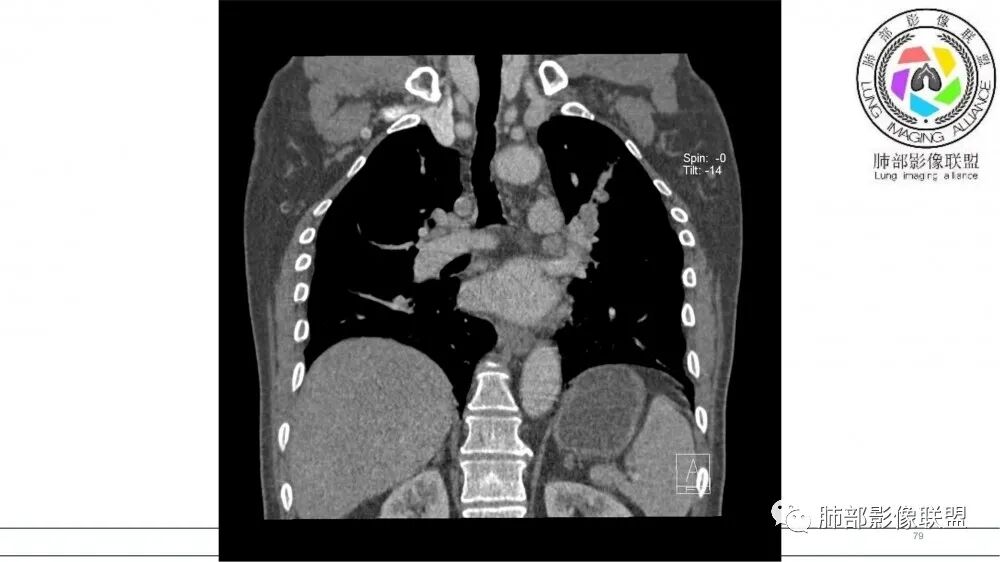

指套征明确吧

有强化吧,淋巴结大

恶性

若尘:

指套征,扩张支气管内软组织强化,远侧肺野阻塞性炎,纵隔、左肺门肿大淋巴结;老年男性,吸烟,考虑鳞癌,鉴别小

2021年8月6日晨读病例结果:小细胞肺癌